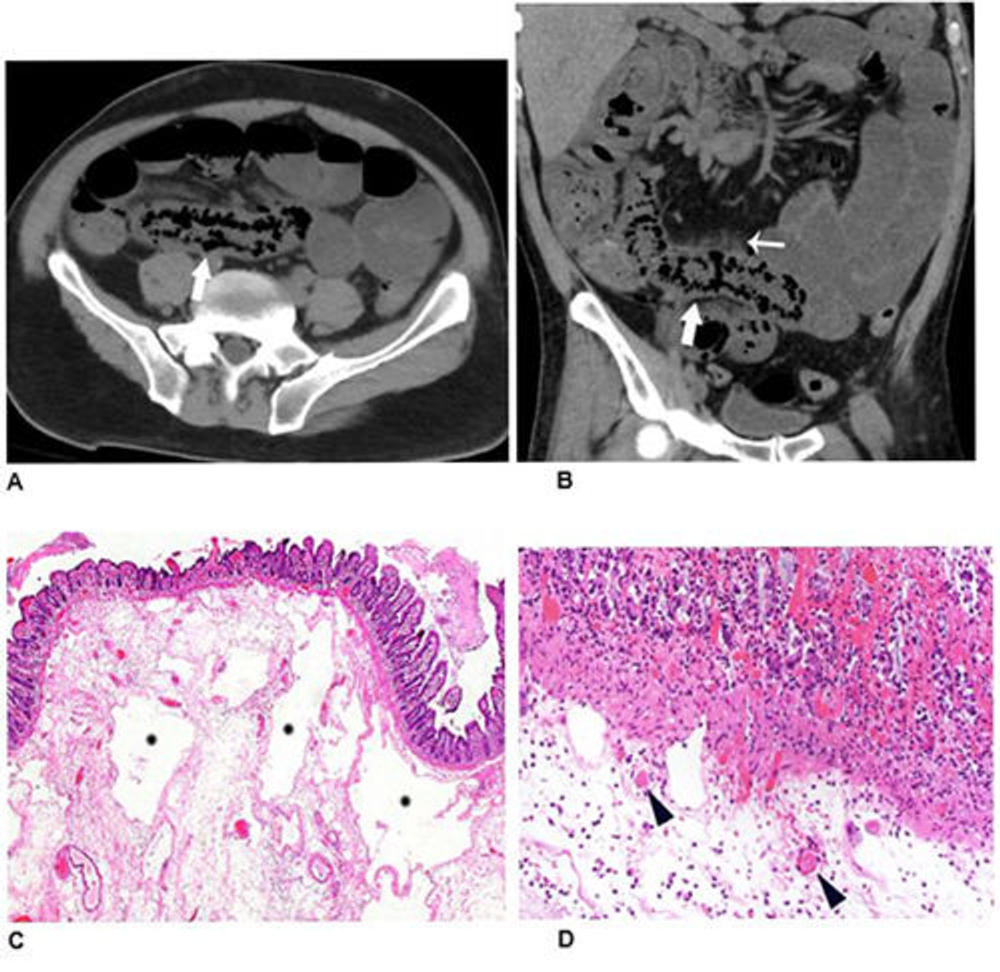

Figure 3. Abdominal radiograph (A) in a 52-year-old man demonstrates portal venous gas (thin arrow in A), suggestive of bowel infarction. Post-operative CT (B) also demonstrates portal venous gas (thin arrow in B). At laparotomy, ischemic and necrotic bowel was identified along with an atypical yellow discoloration of small bowel. Photomicrograph (H and E, 400x) (C) demonstrated submucosal arterioles with fibrin thrombi (arrowheads). The overlying mucosa (upper right) is partially necrotic with crypt dropout and partial loss of the surface epithelium.